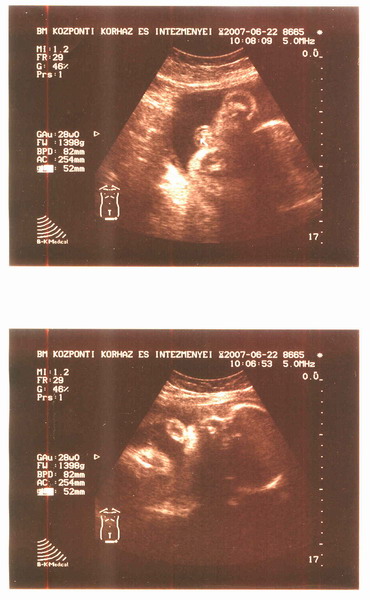

Most voltam a BM Kórház UH-ján, és hát kisfiam lesz:)

Apja nagyon örül, meg persze én is, minden ok, holnap megyünk azért 4 D-re.